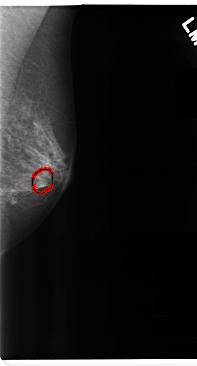

C_0237_1.LEFT_MLO

LEFT_MLO LINES 4752 PIXELS_PER_LINE 2552 BITS_PER_PIXEL 12 RESOLUTION 50 OVERLAY

FILE: C_0237_1.LEFT_MLO.OVERLAY

TOTAL_ABNORMALITIES 1

ABNORMALITY 1

LESION_TYPE MASS SHAPE OVAL MARGINS CIRCUMSCRIBED

ASSESSMENT 4

SUBTLETY 4

PATHOLOGY BENIGN

TOTAL_OUTLINES 1

BOUNDARY